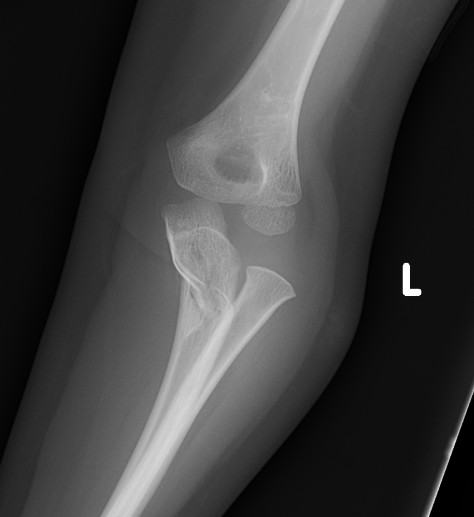

Monteggia

Definition

Fracture / plastic malformation of proximal ulna with dislocation of radial head

Xray

Radio-capitellar line disrupted